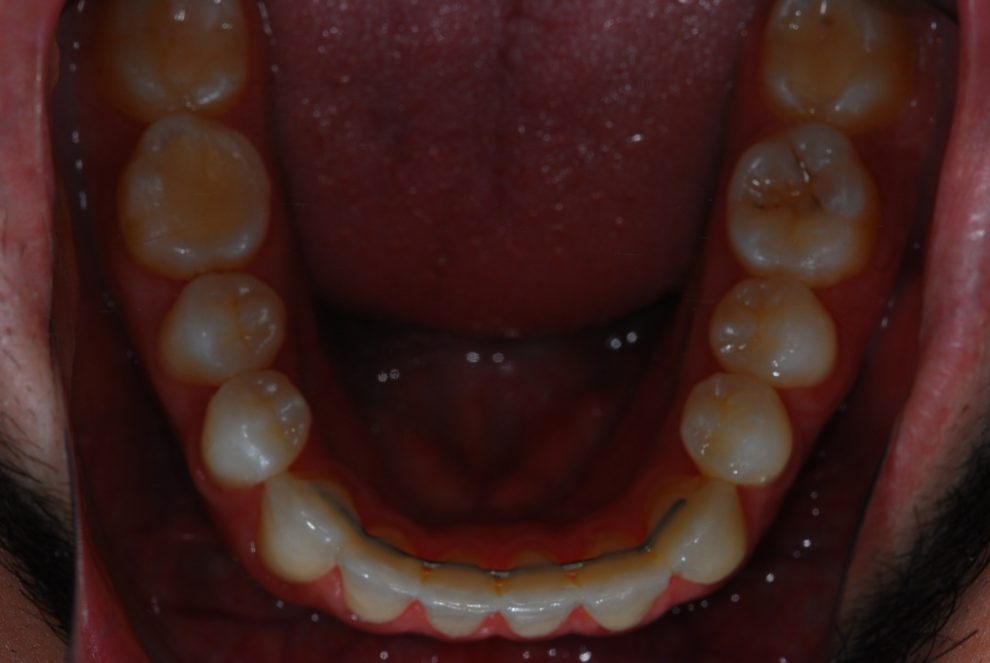

Ortodoncia + Mordida abierta

Nuestro paciente Manuel Vergara Gil acudió a nuestra clínica, y se le hizo una Ortodoncia.